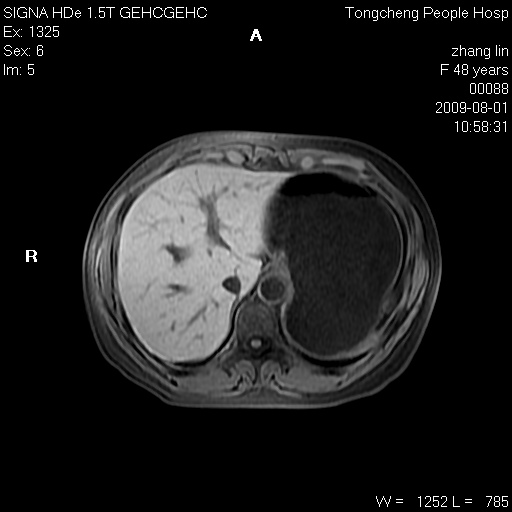

女,48岁。健康体检,彩超发现右肾占位性病变。平素健康。

临床诊断:右肾占位性病变,性质待定(囊肿?肿瘤?)。

上中腹部mr平扫+增强扫描,图像如下:

右肾上极见一类圆形病灶,t1wi呈等信号t2wi呈等高混杂信号,三期增强无强化,边界清---考虑囊肿出血。

同反相位均表现为等信号,病变无强化,考虑含蛋白的囊肿可能,弥散加权相或许有些帮助,